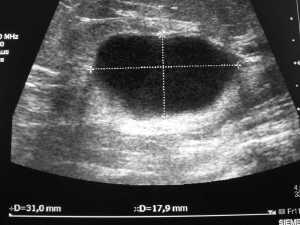

Als Ultraschallluntersuchungen werden in meiner Ordination die ergänzende Mammasonographie,also die Ultraschalluntersuchung der Brust durchgeführt.Des weiteren biete ich Utraschalluntersuchungen der Oberbauchorgane, der Nieren, sowie der Unterbauchorgane an, außerdem noch alle Weichteile, wie Schilddrüse, Sehnen und Gelenke.

Vorbilder Ultraschalluntersuchung: